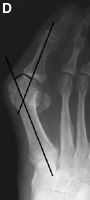

Hallux Valgus Angle

The hallux valgus angle (HAV) or hallux abductus angle is the angle formed between the longitudinal axis of the first proximal phalanx and the longitudinal axis of the first metatarsus.

Hallux VarusA.  In hallux varus or adductus the HAV is less then 5º. Normal Hallux Valgus Angle B. In normal subjects  HAV is 5º to 15º . Hallux abducto valgus is mild when HAV is 16º to 25º,Moderate Hallux Valgus C. moderate  when HAV is 26º to 35º, and severe Severe Hallux Valgus(D) when HAV is greater than 35º.